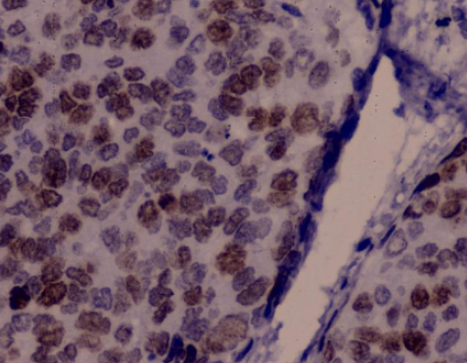

상피내암(Carcinoma in situ)은 암세포가 상피층에만 존재하고, 기저막을 침범하지 않은 상태를 말합니다.

1️⃣ 자궁경부 상피내암

가장 흔하게 언급되는 상피내암입니다.

발생 원인

- HPV(인유두종바이러스) 감염

발견 방법

- 자궁경부 세포검사

- HPV 검사

증상

초기에는 거의 무증상

→ 정기검진에서 발견되는 경우가 대부분치료

2026년 기준, 조기 치료 시 완치율 95% 이상 보고

재발률은 낮지만 추적 관찰 필요